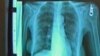

Seorang pasien kanker paru-paru menunjukkan gambar paru-paru sebelah kirinya yang hilang (setelah dioperasi) (Foto: dok).

Para peneliti medis telah menemukan bahwa kanker paru-paru dapat tetap jinak selama lebih dari 20 tahun, kemudian tiba-tiba berubah menjadi ganas. Para pakar yang menulis dalam jurnal “Science” mengatakan ini membantu menjelaskan mengapa penyakit itu sulit diobati.

Para peneliti mengatakan bahwa apa yang mereka gambarkan sebagai cacat genetika dapat tidak terdeteksi selama bertahun-tahun sebelum cacat lain tiba-tiba memicu pertumbuhan cepat kanker tersebut. Menurut para peneliti tersebut, merokok merupakan satu penyebab utama cacat awal.

Mereka mengatakan penelitian itu dapat membantu mereka memahami bagaimana kanker paru-paru berevolusi. Kanker paru-paru adalah bentuk penyakit itu yang paling banyak membunuh manusia. Para dokter mengatakan kemungkinan selamat dari penyakit itu sangat rendah.